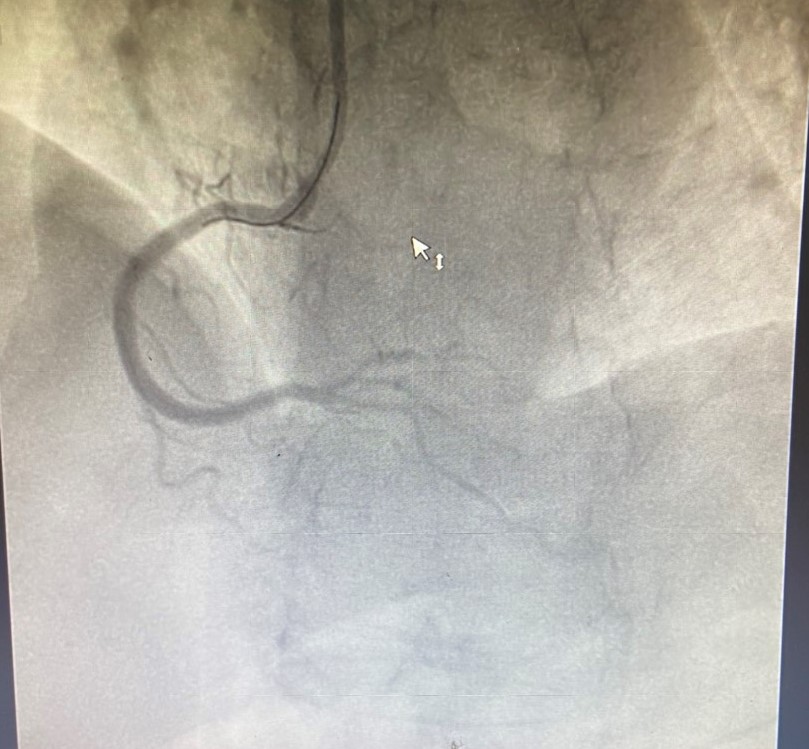

Bệnh nhân ngay sau đó được chỉ định chụp động mạch vành qua da, kết quả chụp xác định tổn thương dài, lan tỏa, hẹp 99% động mạch vành phải; 80-90% động mạch mũ, xơ vữa hẹp rải rác 50% động mạch liên thất trước. Dựa vào điện tim và lâm sàng, các bác sĩ đánh giá thủ phạm dẫn đến nhồi máu cơ tim lần này chính là động mạch vành phải gần tắc hoàn toàn của bệnh nhân. Nếu không được can thiệp kịp thời sẽ nguy hiểm đến tính mạng của người bệnh. Khi ấy, kíp Ths.BSNT Vũ Học Huấn – Trưởng Khoa Tim mạch – Đột quỵ, Ths.BS Phạm Văn Thuận cùng cộng sự đã nhanh chóng tiến hành kỹ thuật can thiệp đặt 2 stent động mạch vành phải thành công. Kết quả can thiệp tốt, ghi nhận sau đặt mạch vành tái thông, bệnh nhân hết đau ngực, nhịp tim cải thiện, sức khỏe dần phục hồi.